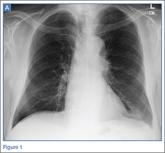

Emergency Imaging: Shortness of breath

- Author:

- Kathryn Dean, MD

- Keith D. Hentel, MD, MS

- Jessica Fisher, MD